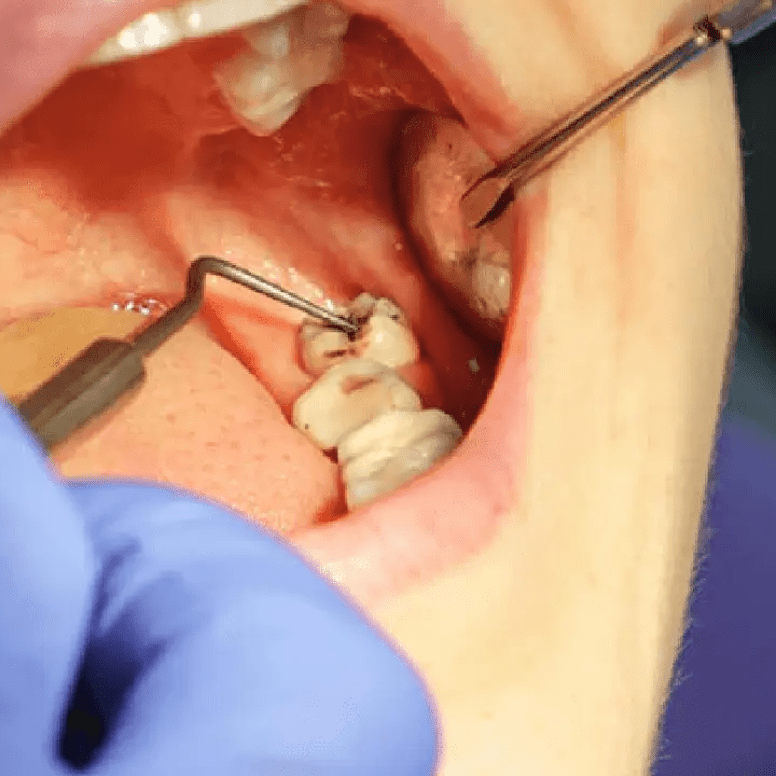

Our high-power microscopes provide extreme precision during Microscopic Root Canal Treatment (RCT). This ensures accurate results and helps save your natural tooth structure.

I recently had a root canal procedure and capping of the tooth done at Dr Renu's dental clinic, and I couldn’t be more pleased with the experience. Dr. Renu and her entire staff were exceptional. From the moment I walked in, I was greeted with warmth and professionalism. The procedure was explained thoroughly, and Dr. Renu ensured I was comfortable throughout. The entire team demonstrated great expertise and care, making a potentially stressful experience quite pleasant. The follow-up care has been impeccable, and I’m delighted with the results. I highly recommend Dr.Renu and her team for anyone seeking top-notch dental care."